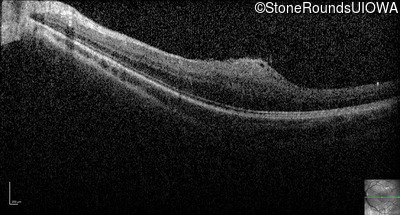

Optical Coherence Tomography - Left - 20/100

Exemplar / OCT Stack